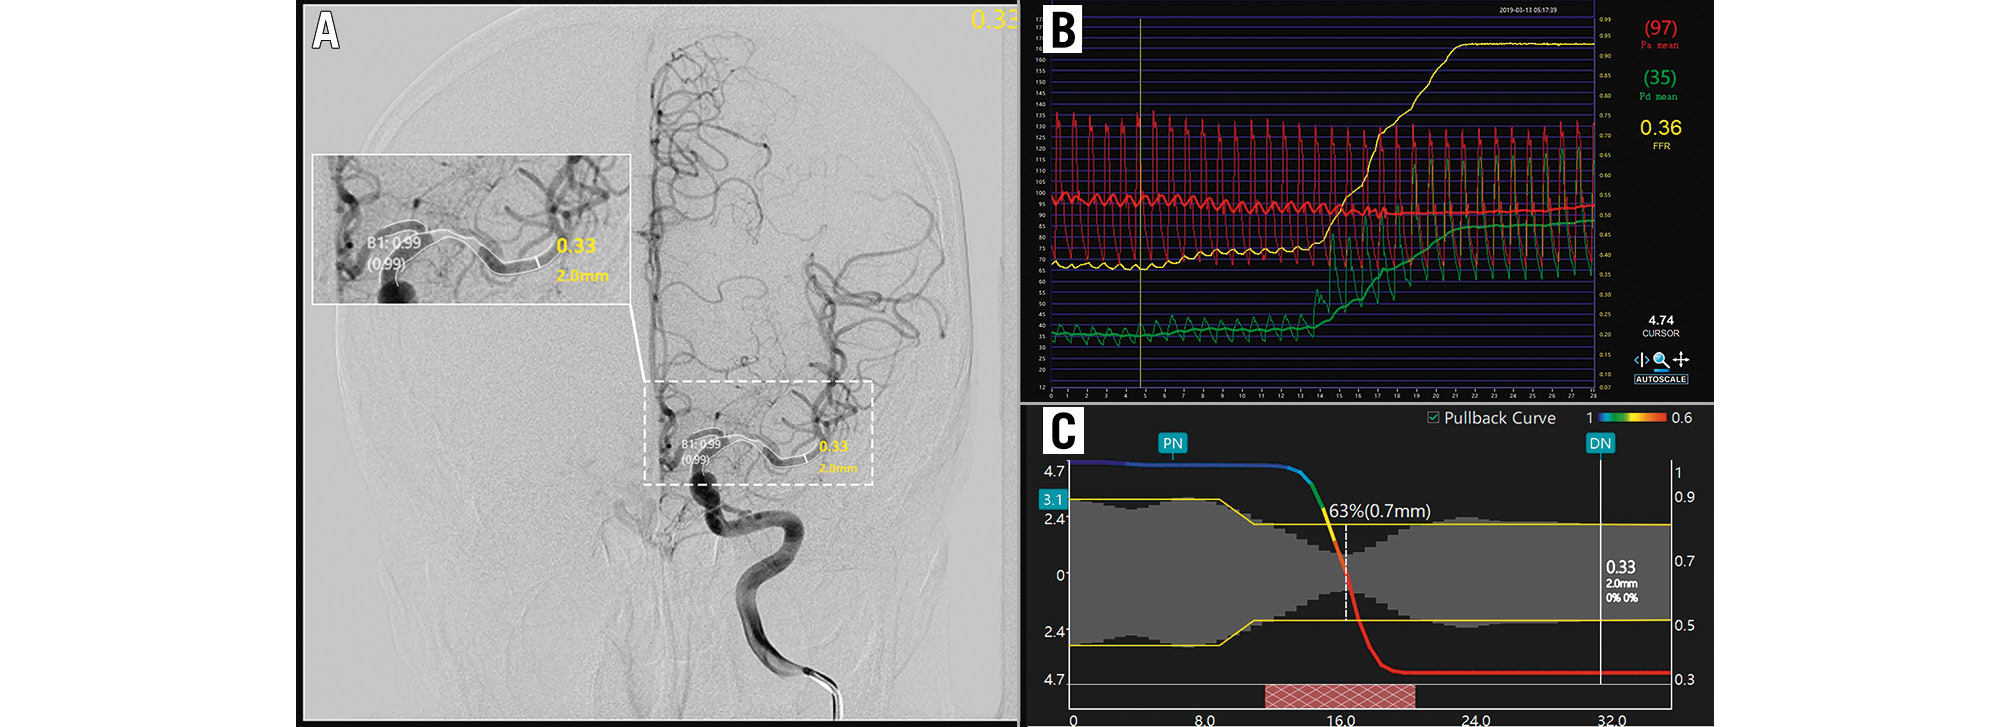

For cerebrovascular stenosis lesions, the μQFR was defined as the pressure ratio distal to and proximal to the stenosis in a fully expanded segment without hyperaemic stimulation. An illustrative example is shown in Figure 1. The core steps are summarised as follows. a) The frame with the sharpest lumen contour at the stenotic segment was selected for analysis. b) The lumen contours of the interrogated vessels and their main side branches were automatically delineated by artificial intelligence. c) The step-down reference vessel size was reconstructed according to the Murray fractal law. d) After the structural acquisition, the pressure drop was calculated according to fluid dynamics equations23 based on the empiric mean flow velocities (0.60 m/s of MCA)2425, assuming blood density and viscosity of 1,060 kg/m3 and 0.0035 kg/m·s, respectively. Finally, the μQFR of the interrogated vessel and its branches were available from the software. A lower μQFR indicated more severe flow limitation.

Figure 1. An illustrative example of the computation of μQFR and FFR. A) Moderate stenosis of the left MCA. The contours of the lumen were automatically delineated and overlaid onto the angiography image. The wire-based FFR (Pa/Pd) was 0.36 (B), while the computed μQFR at the lesion was 0.33, corresponding to a remarkable pressure drop in the pullbacks (C).; FFR: fractional flow reserve; MCA: middle cerebral artery; Pa: aortic pressure; Pd: distal coronary pressure; μQFR: Murray law-based quantitative flow ratio